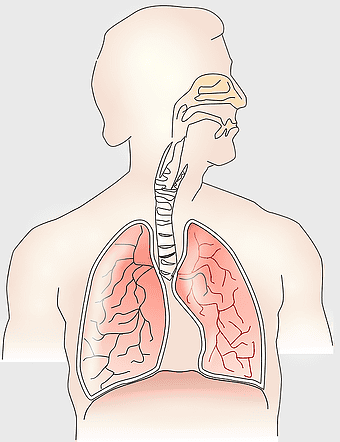

Respiratory system anatomy, human breathing process, pulmonary alveoli structure, respiratory therapist training, respiratory health education, lung function diagram, respiratory disease prevention -